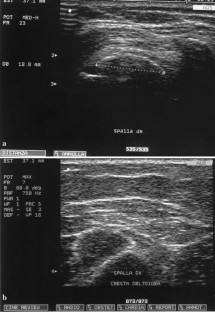

Fig. 2